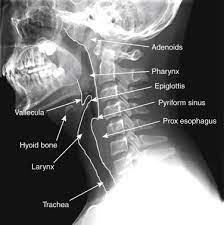

Neck Xray Lateral

Xray Neck Region Lateral View-Pkk